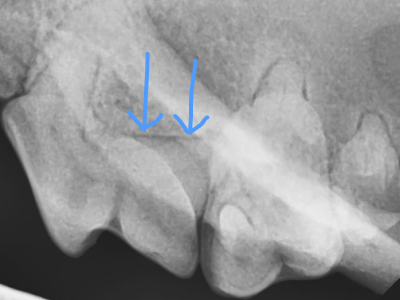

治療前X線

X線で確認するとやはり根っこの周りの骨が歯周病によりなくなっています。

治療5ヶ月後X線

5ヶ月後のX線で骨が再生してきているのが確認できます。

これで大事な噛む時に必要な歯を維持できます。